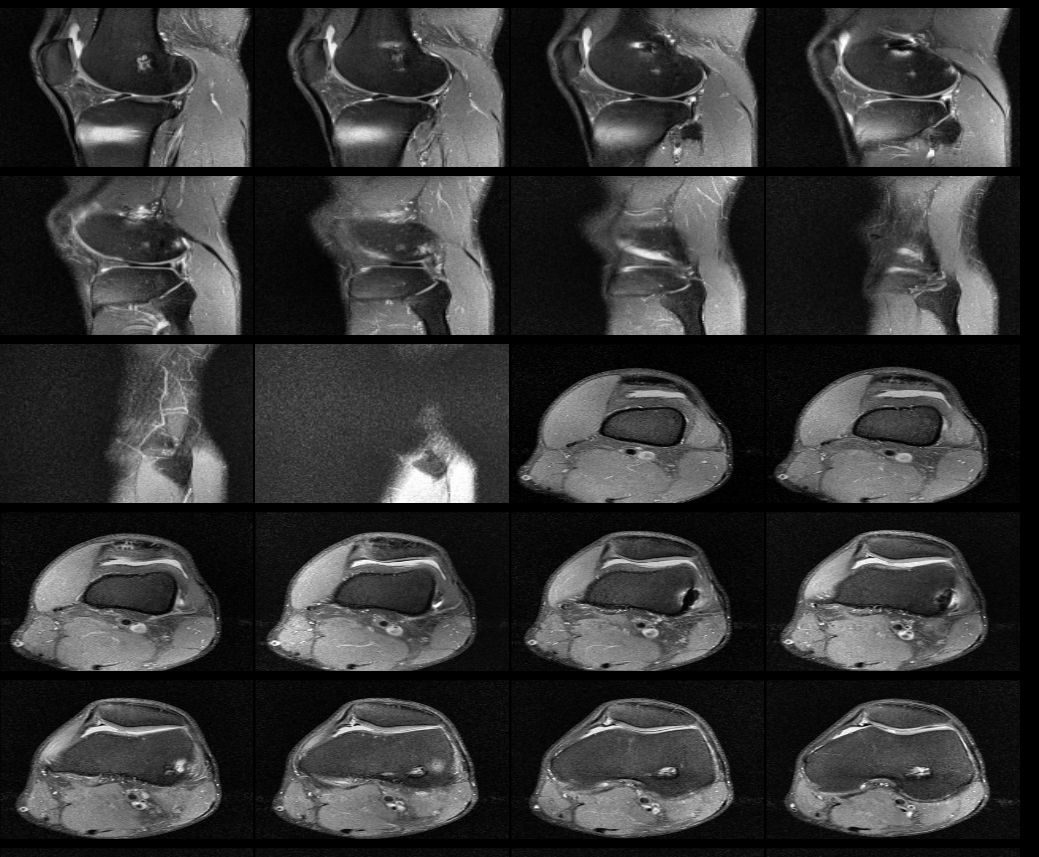

무릎 십자인대 재건술 후 약8년이 지난 지금 mri를 찍었습니다. 판독부탁드립니다ㅠㅠ

약 8년전 무릎 전방십자인대 재건술을 했는데 , 운동관련 직종이다 보니 , 운동을 많이 합니다.

최근들어 무릎에 불편한 통증이 있어 mri를 찍었는데 ,

활막염이라는 말만 들었는데 , 여러 선생님들의 의견을 듣고 싶어 사진올립니다. 판독해주시면 정말 너무너무

안녕하세요. 채홍석 의사입니다. MRI 퀄리티가 나빠서 판독은 어렵겠네요.